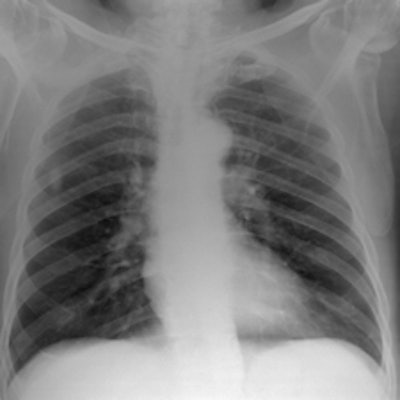

Simulated chest images of an average-sized patient reconstructed at 50 kVp (a) and 150 kVp (b). Image (a) is of higher contrast, which is expected. All images courtesy of Craig Moore.For average-sized patients, image quality improved when tube potential was reduced compared with the reference (102 kVp) and no scatter rejection was indicated. For obese patients, it has been shown that an antiscatter grid is indicated and should be used in conjunction with as low a tube potential as possible (while allowing exposure times, 20 msec), the researchers wrote. It is also possible to reduce receptor air kerma by 50% without adversely influencing image quality. They also found rib contrast did not interfere at any tube potential.

In 50 average patients who were reconstructed without scatter rejection, readers gave higher marks for images acquired with lower tube potential (kVp) settings, demonstrating that image quality improves with lower kVp, the researchers said. Visual grading analysis system scores ranged from 0.41 for 50 kVp to 0.03 for 109 kVp, but there was very little difference between image quality at tube potentials greater than 102 kVp (0.03 at 109 kVp to 0.07 at 150 kVp), according to the authors.

Simulated chest images of an average-sized patient reconstructed with an antiscatter grid (a) and without a grid (b). Image (a) provides greater detail, especially in the denser regions of the chest, which is expected."Although there is a trend toward increased image quality at low tube potentials, it was only possible to statistically distinguish between 50 and 90 kVp, 80 and 90 kVp, and 80 and 109 kVp," Moore and colleagues wrote. "All other combinations demonstrated p-values > 0.102. Nevertheless, these results show that for matched effective dose, image quality improves with lower tube potentials, which is similar to results reported in the literature."